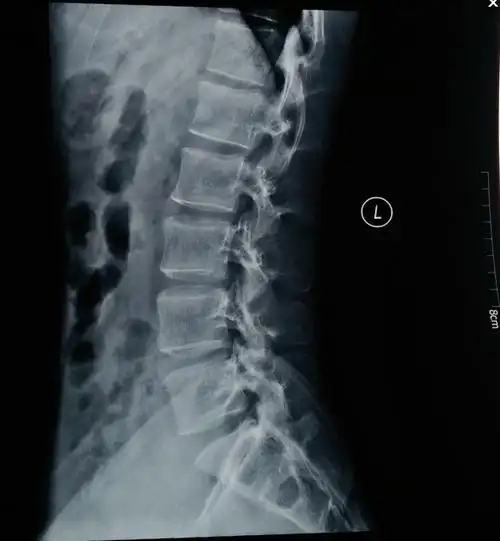

2 ct检查(图2c,d)b.示意图a.骶椎侧位x线片显示s5椎体前缘不光滑1.

看图论病(尾椎骨折)